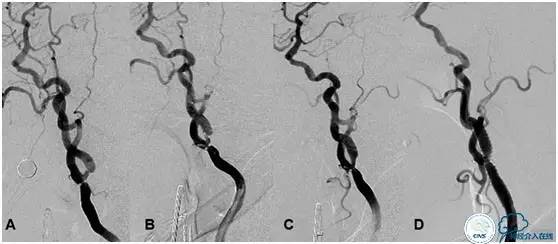

图2:高灌注风险的颈动脉狭窄治疗及随访过程。

A:治疗之前颈动脉侧位图像显示颈总末端和颈内起始部串联重度狭窄;

B:应用2.5mm球囊扩张后造影图像,提示狭窄有所改善,不明显;

C:一期释放支架后,显示残留狭窄超过60%;

D:一个月后造影随访发现残留狭窄明显改善,未进行计划中的球囊后扩张。